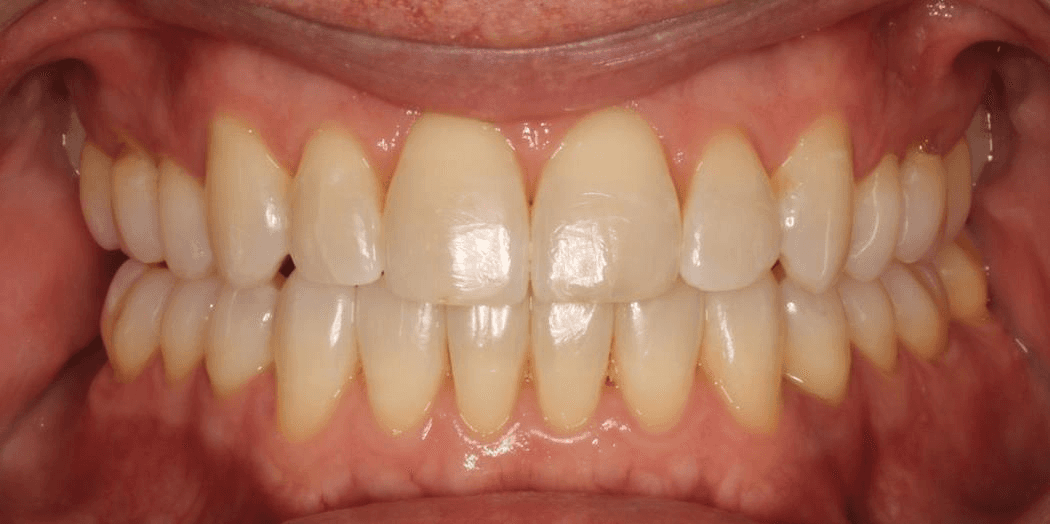

Final results

INTRAORAL